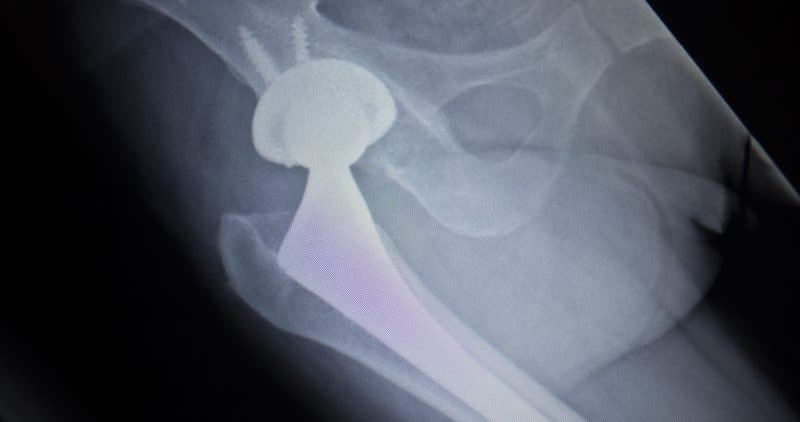

Un juez otorgó $2 millones en daños a un hombre de Albuquerque cuyo implante de cadera defectuoso causó envenenamiento por metal, y la abogada Marie Napoli dice que el veredicto aumentó significativamente el acuerdo...